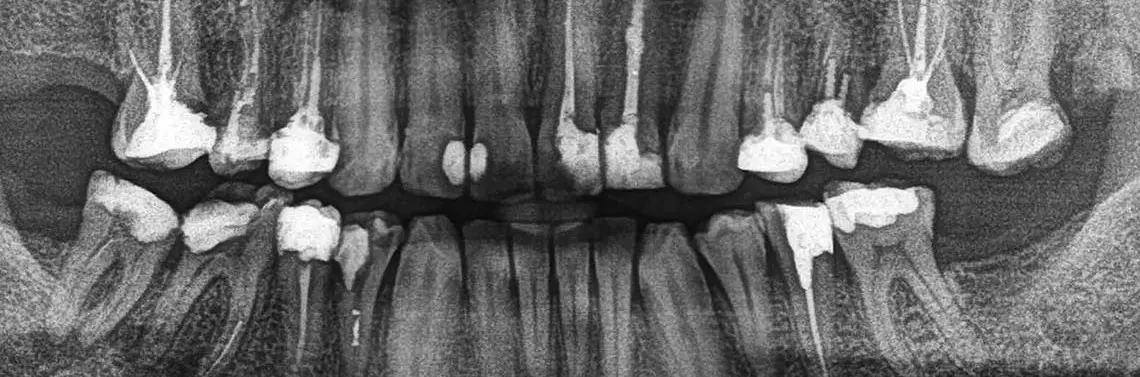

33-letni pacjent, mieszkający na co dzień w Kopenhadze, zgłosił się w celu dokończenia leczenia kanałowego zęba 46. Podczas pierwszej wizyty endodontycznej w innym gabinecie doszło do odseparowania fragmentu maszynowego narzędzia do opracowania kanałów korzeniowych.

Na dostarczonym mi zdjęciu (zdj. 1) widać jeden z kanałów mezjalnych, w którym znajduje się narzędzie o długości odpowiadającej mniej więcej jednej drugiej długości korzenia. Należy zwrócić uwagę na bardzo dużą utratę tkanek twardych k...